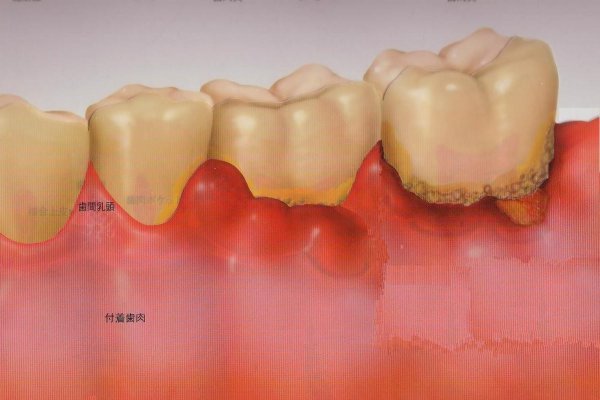

歯周病とは「細菌感染によって歯を支えているあごの骨が溶かされてしまう病気」です。

歯周病の初期は「痛い」「歯が動揺する」などの症状が出ないことが多いため、気づいた時にはすでに進行してしまっている場合が多いという特長があります。歯ぐきから出血する、口の中がネバネバする、口臭が気になる、などの症状に気づいたら、早めの診察を受けましょう。